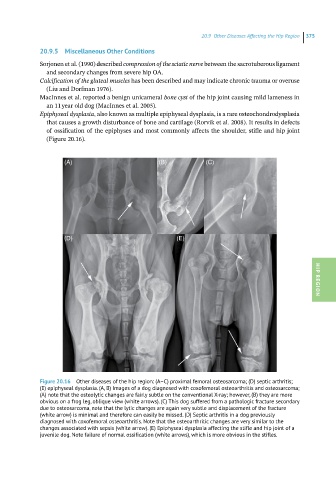

Figure 20.16 Other diseases of the hip region: (A–C) proximal femoral osteosarcoma; (D) septic arthritis;

(E) epiphyseal dysplasia. (A, B) Images of a dog diagnosed with coxofemoral osteoarthritis and osteosarcoma;

(A) note that the osteolytic changes are fairly subtle on the conventional X-ray; however, (B) they are more

obvious on a frog leg, oblique view (white arrows). (C) This dog suffered from a pathologic fracture secondary

due to osteosarcoma, note that the lytic changes are again very subtle and displacement of the fracture

(white arrow) is minimal and therefore can easily be missed. (D) Septic arthritis in a dog previously

diagnosed with coxofemoral osteoarthritis. Note that the osteoarthritic changes are very similar to the

changes associated with sepsis (white arrow). (E) Epiphyseal dysplasia affecting the stifle and hip joint of a

juvenile dog. Note failure of normal ossification (white arrows), which is more obvious in the stifles.